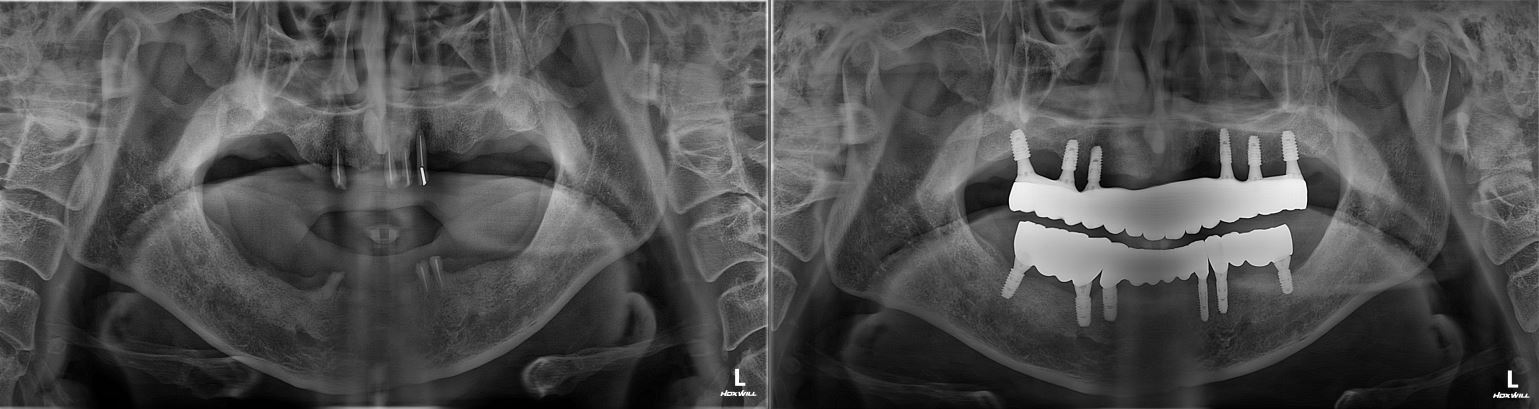

치료전후사진